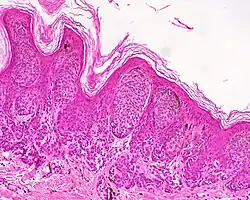

| Compound nevus | Both the epidermis and dermis.[17] |

ICD10: D22 (ILDS D22.L14) ICDO: 8760/0 | |